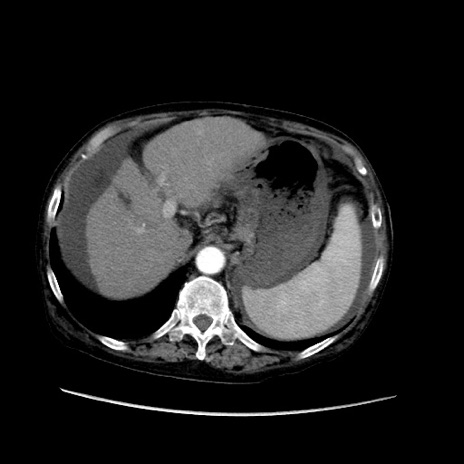

症例31(横断像)

【症例】80歳代 女性

【主訴】腹部膨満感

【現病歴】他院にて肝硬変にてフォロー中。1週間前から便秘、腹部膨満感、臍部腫瘤あり受診となる。

【既往歴】肝硬変

【身体所見】腹部膨隆あり、皮膚変化なし、疼痛なし。

【データ】WBC 4600、CRP 0.25